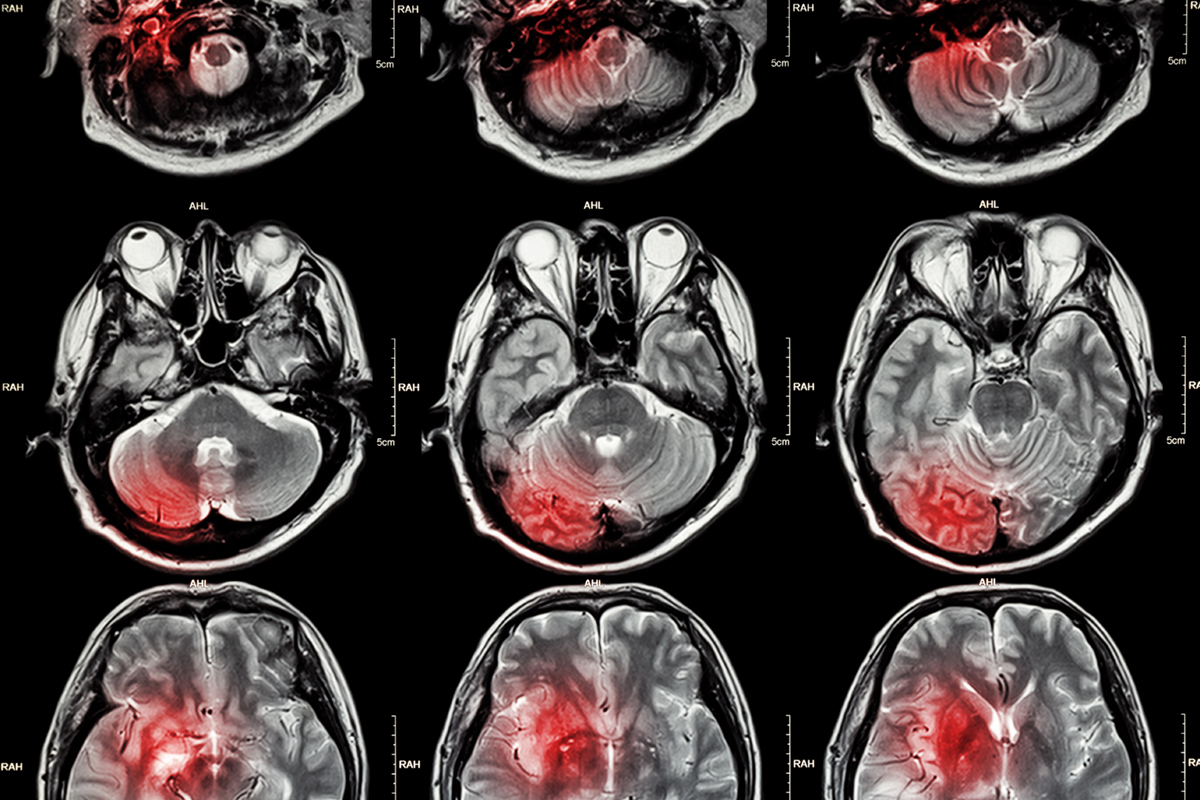

まず同大学研究チームの一員である山崎医局員が、ヒトの脳を解剖して綿密に調べてみると、すべての脳髄の97.7%が脳出血を起こしていることが認められました。

脳出血がみられないのはわずか2.3%ですが、この2.3%は10歳未満の子どもたちで、10歳以上はほぼ100%脳に出血がありました。

しかも、97.7%の脳出血が発見された人のうち、生前、医師がこの患者の脳髄には確かに出血が起こっているはずだ、と診断したのは、わずかに4.7%にすぎなかったのです。

すなわち、卒中の患者や出血性黄疸などと診断された人はわずか4.7%で、あとの93%の人は、自分はもちろんのこと、医師もこの人の脳に出血が起こっているとは分からずにいたということです。

ということは、わたしたちのほとんど全てが、小さい軽度の脳出血を起こしているにも関わらず、それを知らないで生活しているかもしれないということです。